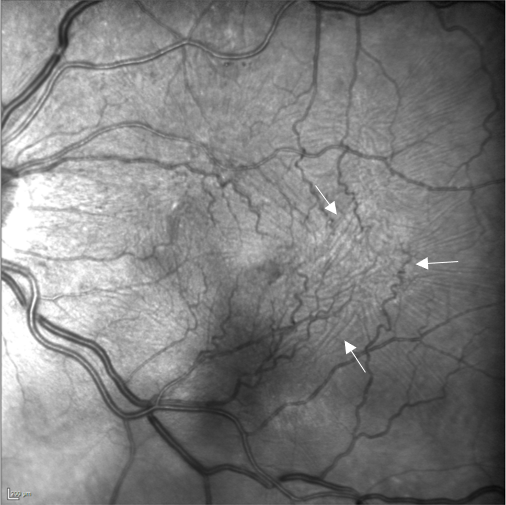

Image Infrarouge 35° : œil gauche avec plis rétiniens (flèches)